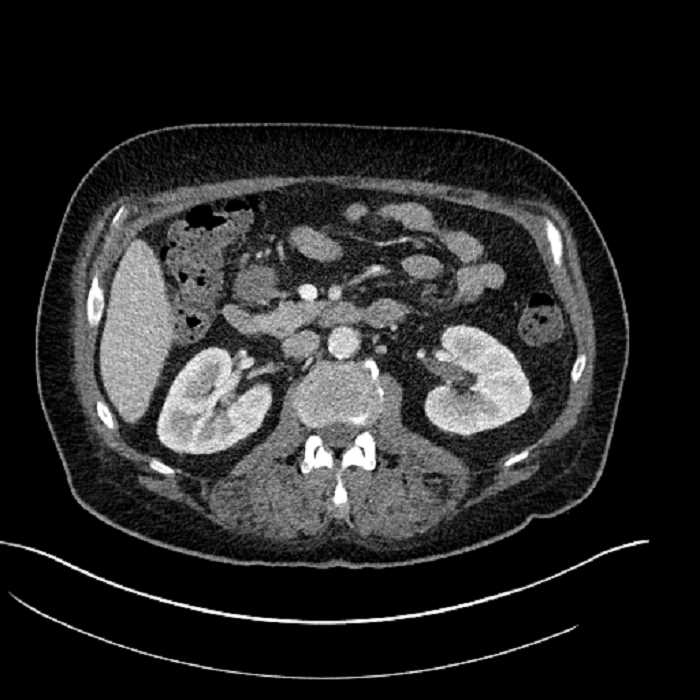

• Mild mural thickening of a segment of the sigmoid colon with adjacent fat stranding and a 1.5 cm fluid and gas collection along the tip of an inflamed diverticulum

• Loss of the normal fat plane between this collection and adjacent loops of small bowel, which demonstrate mural thickening

• No bowel obstruction

• High grade stenosis of the left common iliac artery, with the left internal and external iliac arteries remaining patent

Acute sigmoid diverticulitis complicated by a small contained perforation and a large abscess in the right hepatic lobe. Additional small subcapsular abscesses along the anterior margin of the left hepatic lobe.

Additionally, loss of the normal fat plane between the peridiverticular collection and adjacent thickened loops of small bowel raises the potential for an enterocolonic fistula.

High grade stenosis of the left common iliac artery. The left external and internal iliac arteries are patent.

Hepatic abscess showing the double target sign with low density internally surrounded by a thin inner enhancing rim (red arrow) and ill-defined outer low density rim (yellow arrow). Blue arrow indicates an internal septation. Red arrows: additional smaller subcapsular abscesses. Red arrow: focal contained perforation associated with diverticulitis.